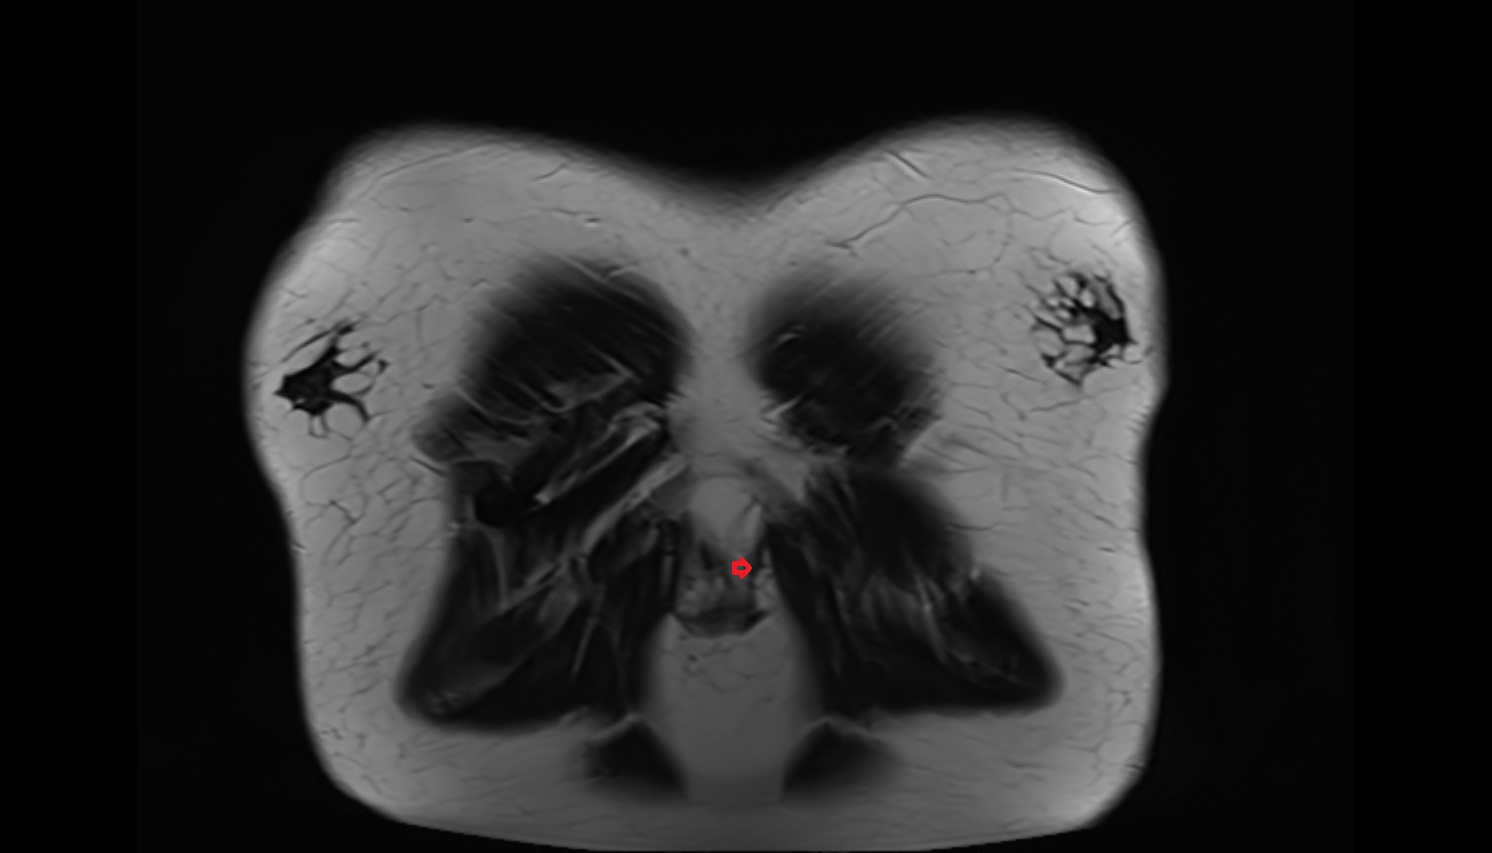

- Anterior cruciate ligament

- Posterior cruciate ligament